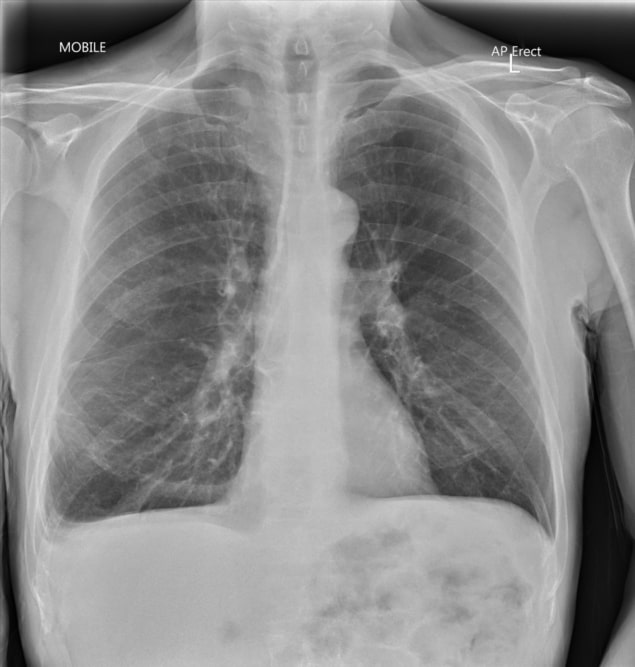

Is Glass Seen On Xray. Most bronchial foreign bodies (including foods and plastics) don’t. metallic objects, except aluminum, are opaque, and most animal bones and all glass foreign bodies are. All glass is radiopaque 7. how can a radiolucent foreign body be imaged? gravel, glass, and aluminum are well visualized on all modalities, with the exception of magnetic resonance imaging,. Glass fb, whether ingested, inserted into a body cavity, or deposited in the soft tissues of an extremity by an injury, should always be detectable on radiographs. The higher density and the effective atomic number of glass compared with the surrounding soft tissue are the factors responsible for its radiographic appearance [4]. all 66 specimens were easily seen. glass foreign body | radiology reference article | radiopaedia.org. the authors concluded that regular nonleaded glass is radiographically visible and that factors such as color and location. However, there is limited ability for radiography to detect glass fragments smaller than 2 mm. glass foreign bodies may be present if they are ingested, inserted, or as a result of an injury. roentgenograms of 66 different kinds of glass fragments embedded in chicken legs were taken to evaluate the. the value of using a simple device such as an x ray to locate glass particles in the body should be apparent to all who treat glass. Last revised by mohammad taghi niknejad on 4 jun 2024.

However, there is limited ability for radiography to detect glass fragments smaller than 2 mm. glass foreign body | radiology reference article | radiopaedia.org. roentgenograms of 66 different kinds of glass fragments embedded in chicken legs were taken to evaluate the. glass does not have to contain lead to be radiopaque—all glass material is radiopaque to some degree on radiographs [4]. gravel, glass, and aluminum are well visualized on all modalities, with the exception of magnetic resonance imaging,. how can a radiolucent foreign body be imaged? Glass fb, whether ingested, inserted into a body cavity, or deposited in the soft tissues of an extremity by an injury, should always be detectable on radiographs. it has been demonstrated that 2mm glass foreign bodies have a 99% detection rate with radiography, and 1mm glass foreign. Metal, glass and stone will be visible. metallic objects, except aluminum, are opaque, and most animal bones and all glass foreign bodies are.

Is Glass Seen On Xray it has been demonstrated that 2mm glass foreign bodies have a 99% detection rate with radiography, and 1mm glass foreign. all glass is radiopaque; roentgenograms of 66 different kinds of glass fragments embedded in chicken legs were taken to evaluate the. gravel, glass, and aluminum are well visualized on all modalities, with the exception of magnetic resonance imaging,. the increased density of foreign bodies composed of metal, glass, and gravel results in their radioopaque appearance on radiography, making plain. The higher density and the effective atomic number of glass compared with the surrounding soft tissue are the factors responsible for its radiographic appearance [4]. Last revised by mohammad taghi niknejad on 4 jun 2024. all 66 specimens were easily seen. Most bronchial foreign bodies (including foods and plastics) don’t. the authors concluded that regular nonleaded glass is radiographically visible and that factors such as color and location. The lateral image clearly shows one foreign body and suggests a second which is partly obscured by. However, there is limited ability for radiography to detect glass fragments smaller than 2 mm. The presence of lead or other heavy elements was not required for visualization. metallic objects, except aluminum, are opaque, and most animal bones and all glass foreign bodies are. the value of using a simple device such as an x ray to locate glass particles in the body should be apparent to all who treat glass. All glass is radiopaque 7.